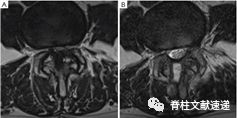

图注:对于严重狭窄的患者,通过单侧椎板切开(虚线)进行双侧减压可能会导致同侧小关节过度破坏(A);从棘突底部移除更多的骨质(*)(双箭头),保留同侧小关节(B)。

图注:术前(A)和最后随访(B)MRI对小关节保存的测量。虚线突出显示椎板切开的范围。小关节保存率=y/x×100%。